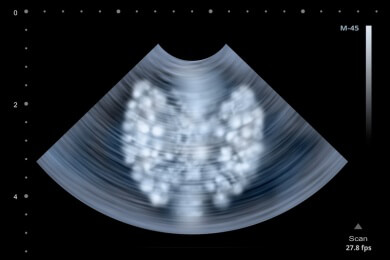

Die Über- oder Unterfunktion wird durch Ultraschall, einer Blut- oder einer Tastuntersuchung diagnostiziert. Die Therapien schlagen in der Regel gut an, vorausgesetzt die Diagnose wird frühzeitig gestellt.